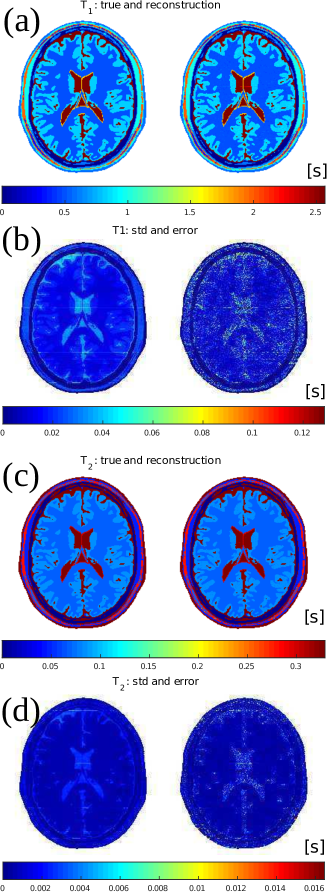

4.2 In-silica high resolution reconstruction

Beside , and , also the transmit field profile and off-resonance map are reconstructed; they are displayed in Figures 6 and 7. They closely agree with the true values. In Table 2, the mean values and corresponding variations over each tissue type are reported and show high precision.

The root-mean-squared-errors (RMSE) for the and maps are also very small, namely:

The reconstruction time is about 90 minutes. The median number of performed iterations as calculated over all parallel reconstruction processes is 13.

The standard deviations estimated by MR-STAT for and are shown, respectively, in Fig. 6(b) and Fig. 6(d). For comparison, the actual error maps, respectively defined as and , are also reported and they show clear similarities.